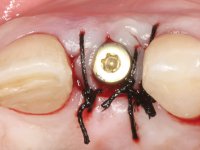

• Placement of an implant at the tooth site 2.2. Rehabilitation of the implant with a coronary and gingival component abutment. in which the screw access hole was "camouflaged" with a feldspathic veneer.

Treatment began with re-preparation of the cast post and core, with the purpose of placing the cervical finishing lines with an intra-sulcular location and simultaneously making a suitable temporary crown. With a very simple orthodontic treatment, the diastema was closed between the upper central incisors, and this position was stabilized with a wire placed on the palatal surface of the central, functioning as containment. Later, a slow orthodontic traction of tooth 2.2 was attempted, in order to reduce, although very slightly, the vertical bone loss in this area. At the end of the traction, tooth 2.2 was extracted and the area was provisionally rehabilitated with a composite resin crown bonded to the adjacent teeth. A dental implant was placed in the area of tooth 2.2 and the temporary crown was again bonded to resin, provisionally rehabilitating the patient during osseointegration. In tooth 1.3 a gingivectomy with an electric scalpel was performed, with the intention of raising the cervical level of 1.3 achieving greater harmony with tooth 2.3. Stabilized soft tissues were impressed using the open tray technique with putty and light addition silicones. Collection of the color of both the dental component and soft tissues was done by the ceramist in the office. In the laboratory, the impressions were transferred to plaster and gave origin to work models that were properly analyzed. It was decided to assemble a metal-ceramic abutment screwed onto the implant. This abutment was cast with a noble alloy and subsequently coated with coronary and gingival ceramics. Due to the inclination of the implant, the screwing inevitably conditioned the exit of the screw hole through the vestibular surface. In order to conceal this situation, the design of the abutment has already been conceived with the intention of accommodating on the vestibular surface the bonding of a feldspathic veneer. This abutment was tested in the mouth and adjustments were made in the gingival ceramic component. Its adaptation to the soft tissues was done in a subtractive way, with a drill, as well as additive, adding resin composed of gingival tonality.

This addition of resin would guide the ceramist in the final placement of the gingival tonality ceramic. The crown that would rehabilitate tooth 1.3 was cemented in this test session with glass ionomer cement, reinforced with composite resin. Once the laboratory work was finished on the veneer for tooth 1.2, the abutment, and the veneer for the implant, this was bonded in the mouth, after placement of the absolute insulation. The work completely satisfied the patient. For eight years, the patient had periodical check-ups, and was pleased with the treatment, but also began to show interest in an aesthetical intervention on the upper central incisors. Once the second phase of our intervention was decided, dental preparation of teeth 1.1 and 2.1 was performed for the placement of two feldspathic veneers. Particular care was taken in the distal inter-proximal preparation adjacent to the abutment of the implant.